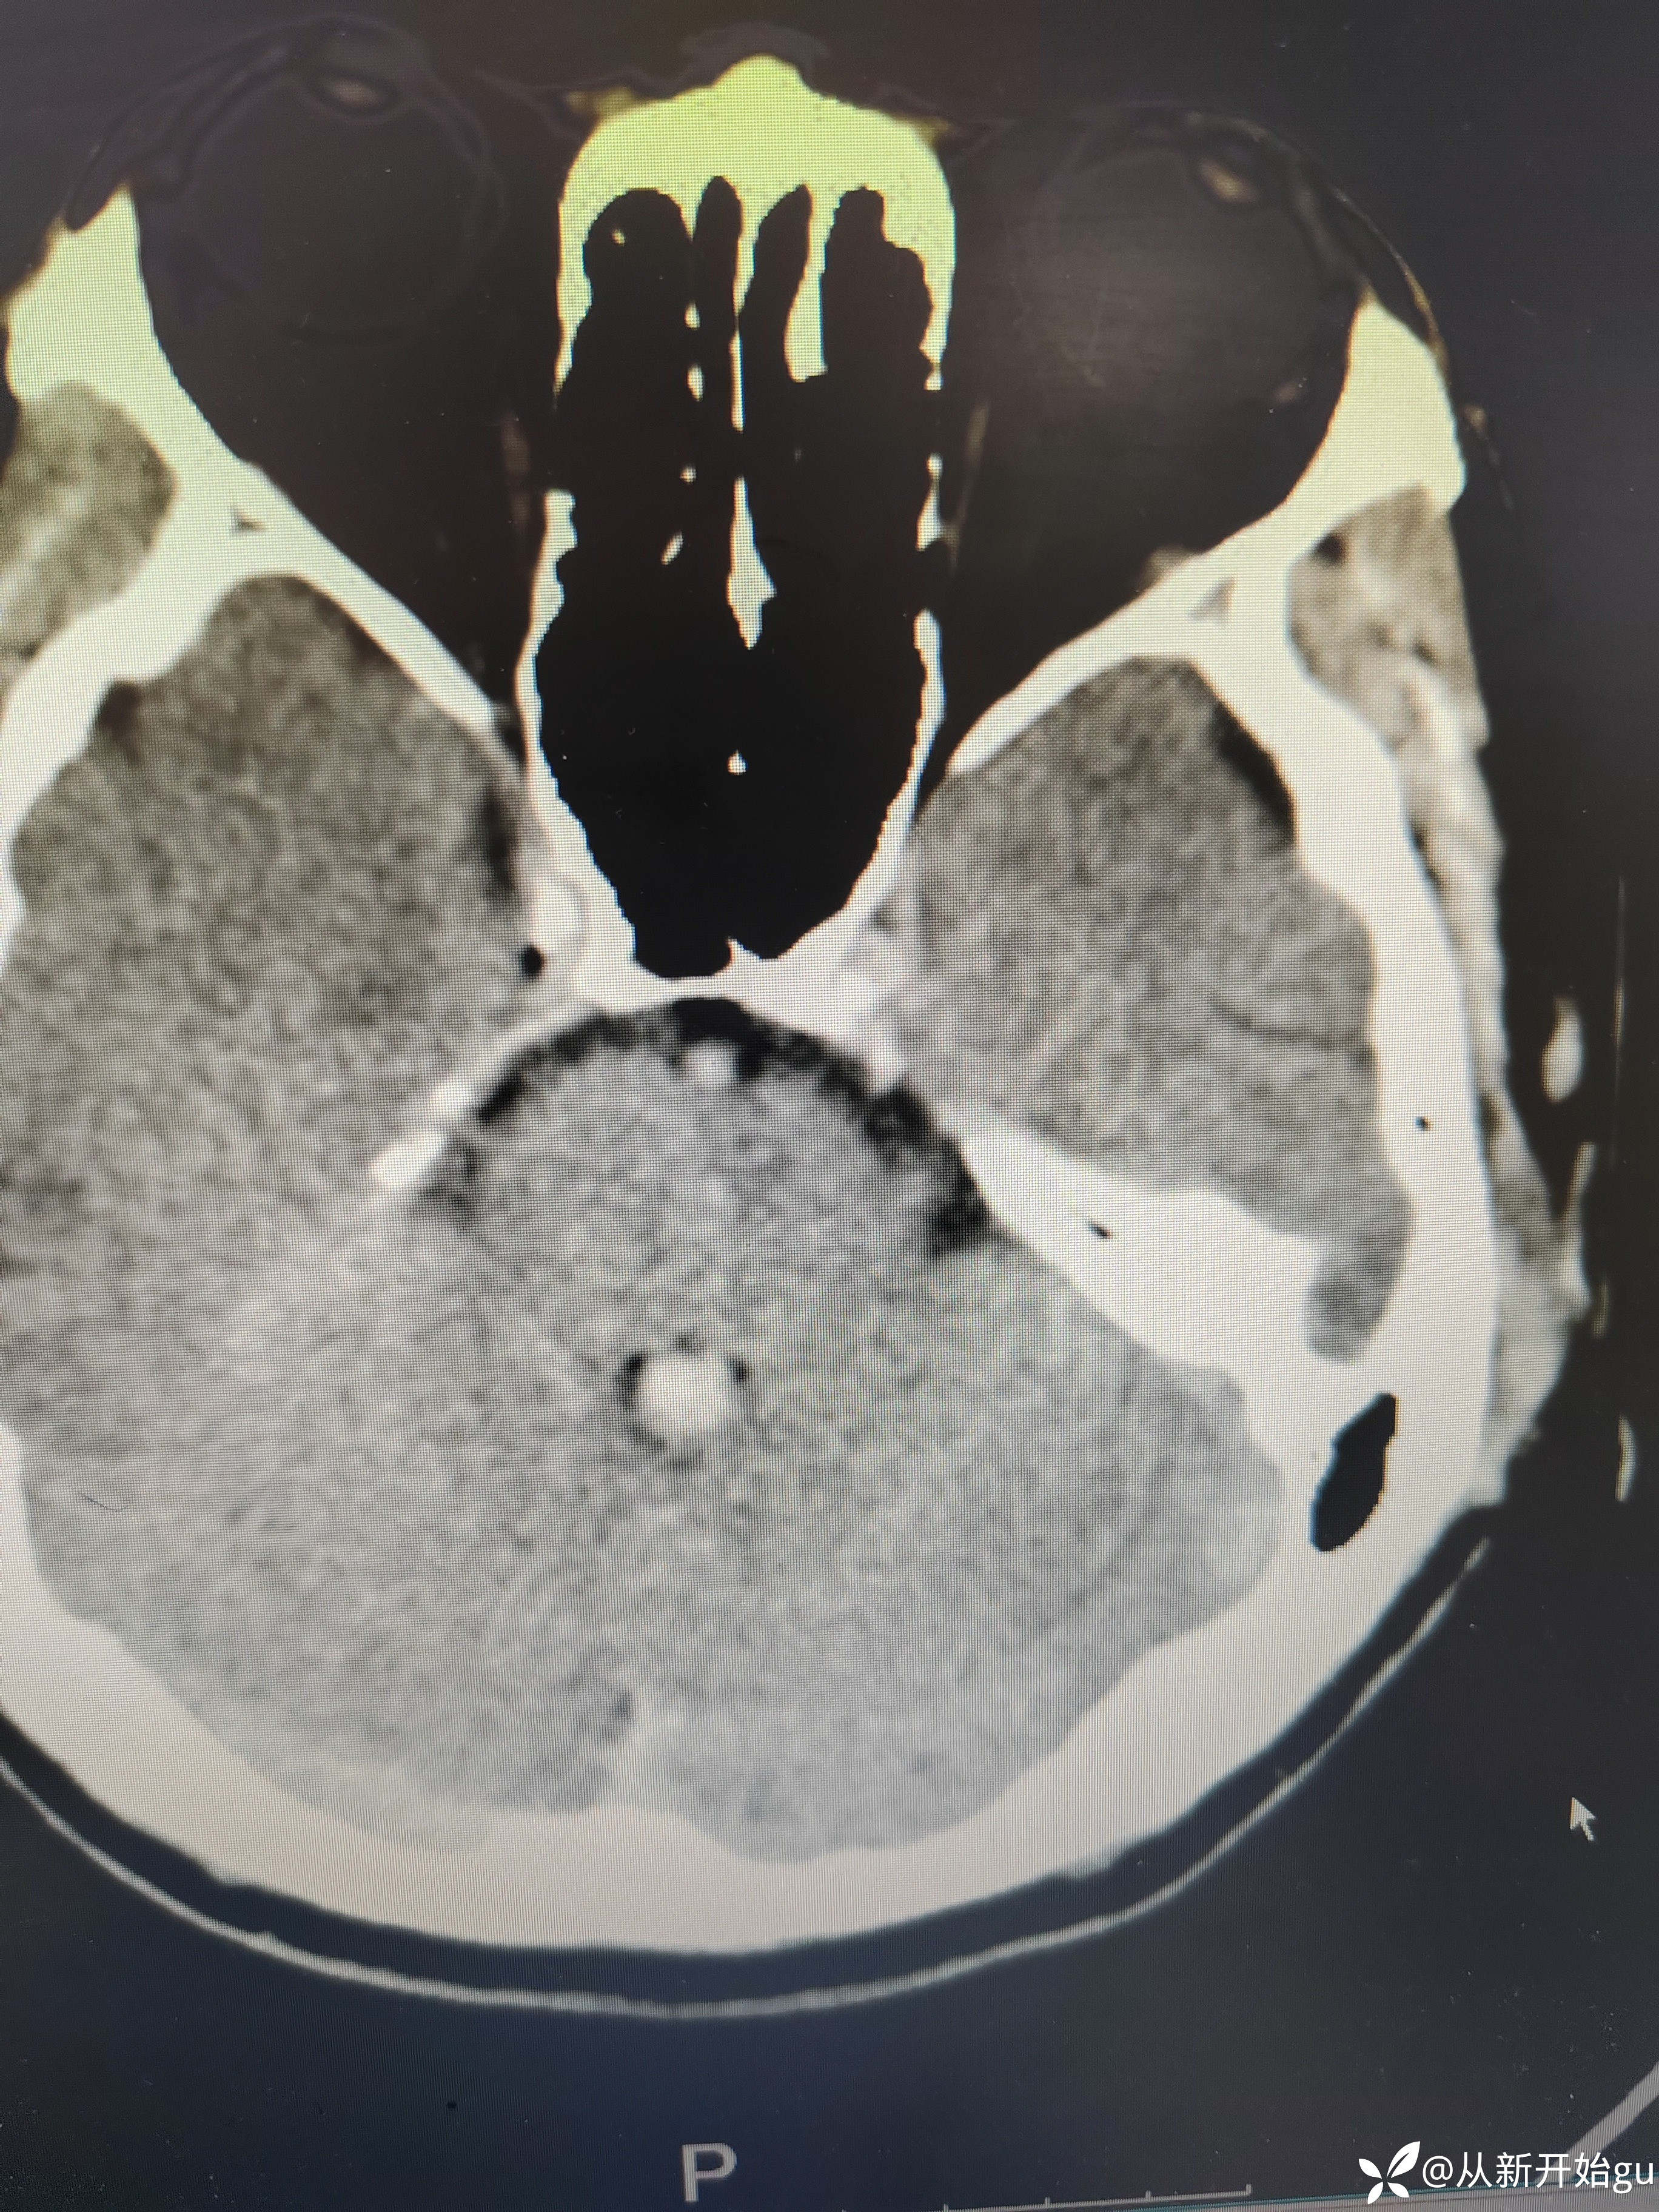

【检查】:完善颅脑CT.

【检查】:完善颅脑CT.